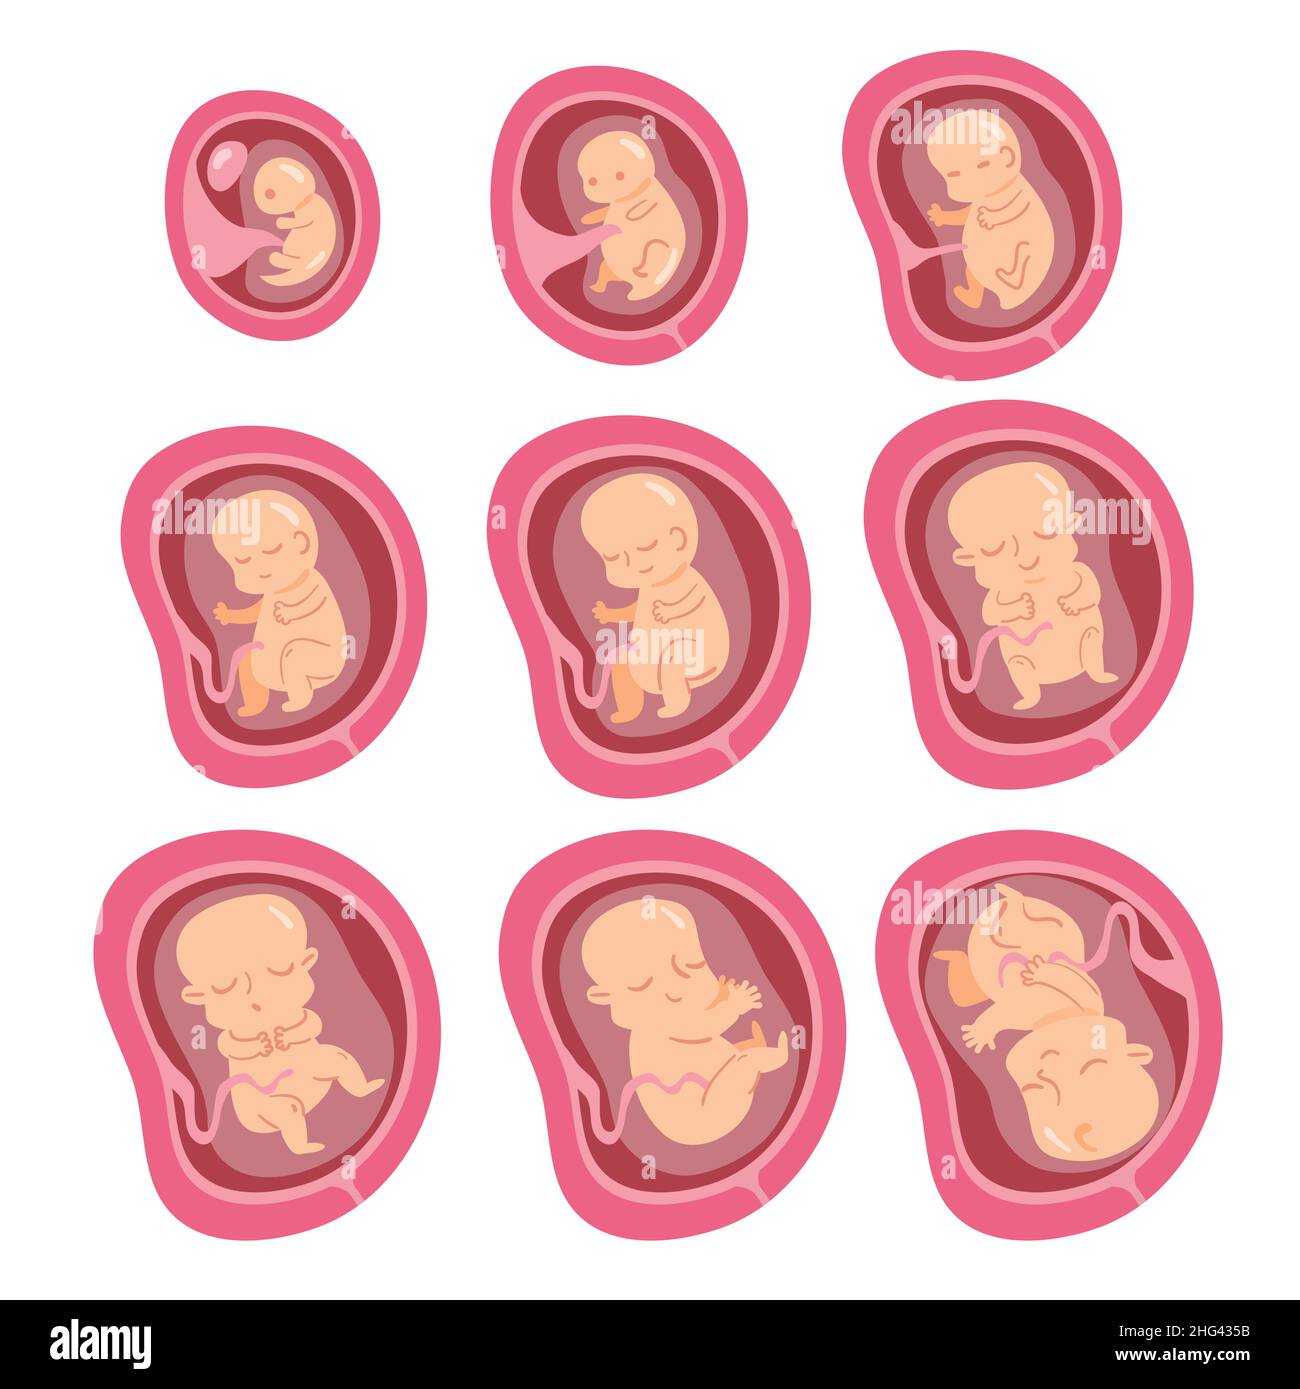

- Fetal Position Background Illustrations, Royalty-Free Vector Graphics ...

- 8,500+ Fetal Baby Stock Photos, Pictures & Royalty-Free Images - IStock